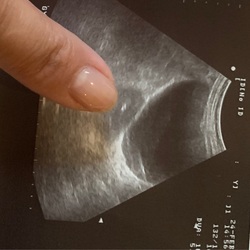

Ik had 5 dagen voor mijn NOD al licht positieve testen! Echter verloor ik wat bloed.. 5 dagen lang.. (volgens verloskundige de innesteling)Daarvoor had ik lage rugpijn en wat steekjes onderin mijn buik. Pijnlijke borsten, moe en stemmingswisselingen. Inmiddels bijna 5 en een halve week zwanger. De 31e de eerste echo.. spannend!